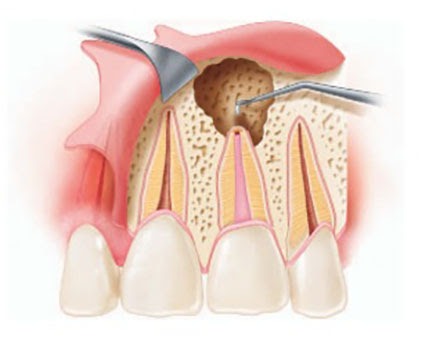

Es un procedimiento en el que se abre la cámara pulpar del diente para eliminar el tejido pulpar infectado o inflamado. Esto ayuda a aliviar el dolor y preparar el diente para un tratamiento de conducto.

Trepanación Pulpar (urgencia)